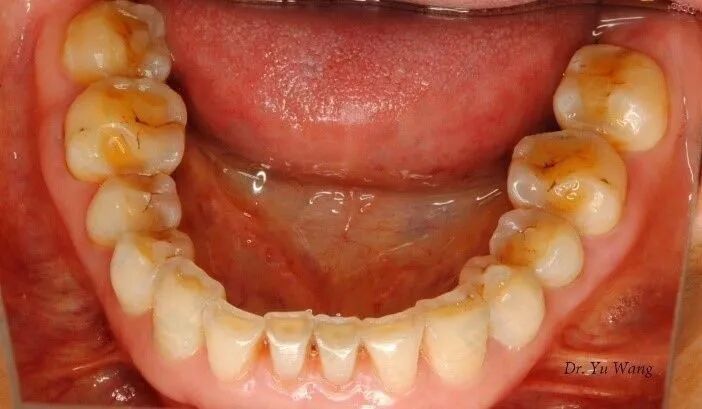

此外,经常夜磨牙的人可能会慢慢磨除外层的牙釉质,暴露其下方淡黄色的牙本质。

牙釉质重度磨耗